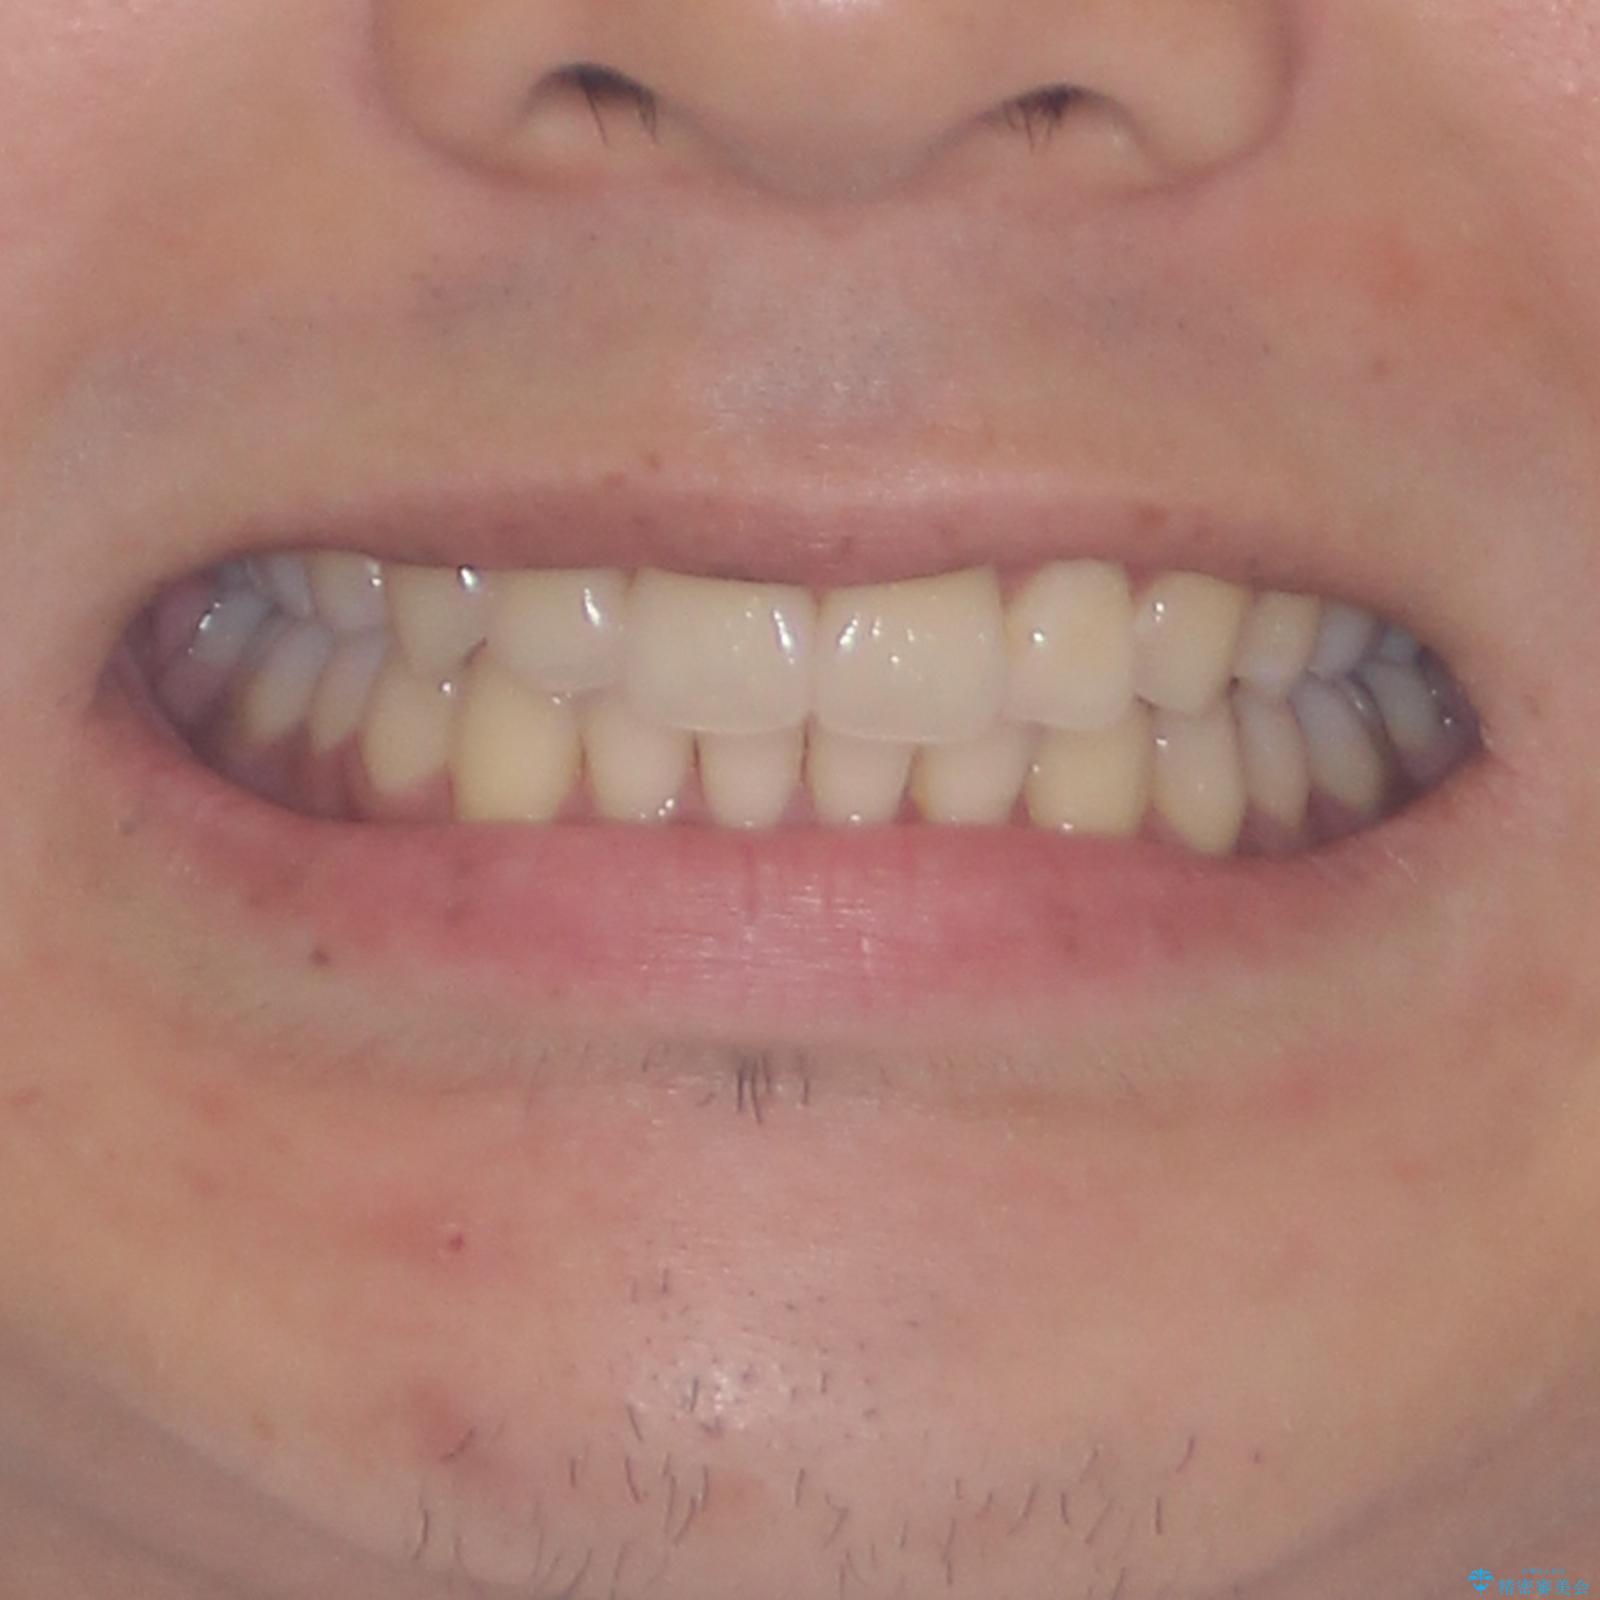

矯正治療の後戻りをインビザライン・ライトで解消

- 矯正治療の後戻りを気にして来院された患者様です。

後戻りは軽微であったので、インビザライン・ライトにより矯正治療を行うこととしました。

インビザライン・ライトは提供されるマウスピースの数に制限があり、通常のタイプよりもマウスピース提供期間が短くなっている一方、安価に治療を行うことができるプランです。

治療のゴールも変更できないため、軽微な歯列不正や、後戻り改善などに適しています。

矯正治療後は、再度後戻りすることを極力回避するために、下顎前歯の舌側を細いワイヤーを用いて保定することとしました。